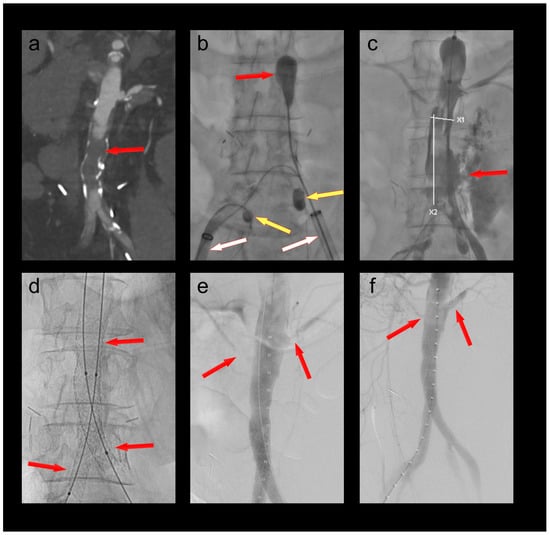

3.1. Patient 1

A 70-year-old male patient who had undergone a 4-fenestration endovascular aneurysm repair (EVAR) 6 months prior was admitted with new-onset short-distance claudication of his right leg. CT angiography revealed a complete occlusion of the right EVAR limb and a non-occlusive thrombus in the left limb. The renal fenestrations/origins of the renal bridging stentgrafts were only a few millimeters above the graft bifurcation (Figure 1). Both renal bridging stentgrafts and the right hypogastric artery were protected using 3F OTW Fogarty® catheters over 0.018″ guide wires. The left hypogastric artery was protected by advancing the sheath into the distal EVAR limb. A thrombectomy of both limbs was performed using a 6F Fogarty® catheter (Figure 1). An iatrogenic dissection of the right renal artery at the distal end of the bridging stent graft was treated by implantation of a 5 × 25 mm Gore® Viabahn self-expandable stent graft. Postoperative CT-scan showed complete thrombectomy of both limbs and ruled out any embolization of the renal and hypogastric arteries (Figure 1).

The same patient was treated a second time one year later using the same technique for an occlusion of the contralateral EVAR limb.

Foot pulses were palpable bilaterally after both procedures.

Figure 1. (a) Thrombotic occlusion of the right EVAR limb (ballerina situation) (red arrow); (b) thrombectomy of the graft limb (red arrow) under balloon protection of both renal bridging stentgrafts and the right hypogastric artery (yellow arrows). The large-bore sheaths are occlusive in the left graft limb and in the right external iliac artery (white arrows); (c) Iatrogenic dissection of the right renal artery (red arrow); (d) Right renal artery after implantation of a self-expanding stent graft (red arrow).